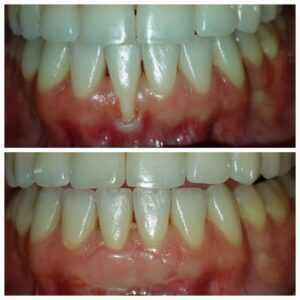

Before

Soft Tissue Grafts Before

After

Soft Tissue Grafts After

Exposed tooth roots are the result of gum recession. The procedure for preventing additional bone loss and recession is called gum graft surgery. Soft Tissue Grafts, which provide regeneration of your gums, is a procedure that can be done prior to Porcelain Crowns that your General Dentist provides.

The goal is to create a zone of gum tissue to prevent further recession and to attain whatever root covering as possible. The root coverage is not guaranteed and not the primary goal of the graft.

Soft Tissue Grafts can be used to cover exposed roots and handle excessive gingival recession that is the reason for the lack of gum tissue. The procedure assists in developing additional gum tissue. During gum graft surgery, Dr. Fialkoff will cover the exposed root for one tooth or several teeth. The goal is to even your gum line and reduce the sensitivity in your mouth.

Please note that covering the roots is unpredictable and no guarantee can be given as to the final coverage or lack of. These pictures are only examples and not guaranteed results.